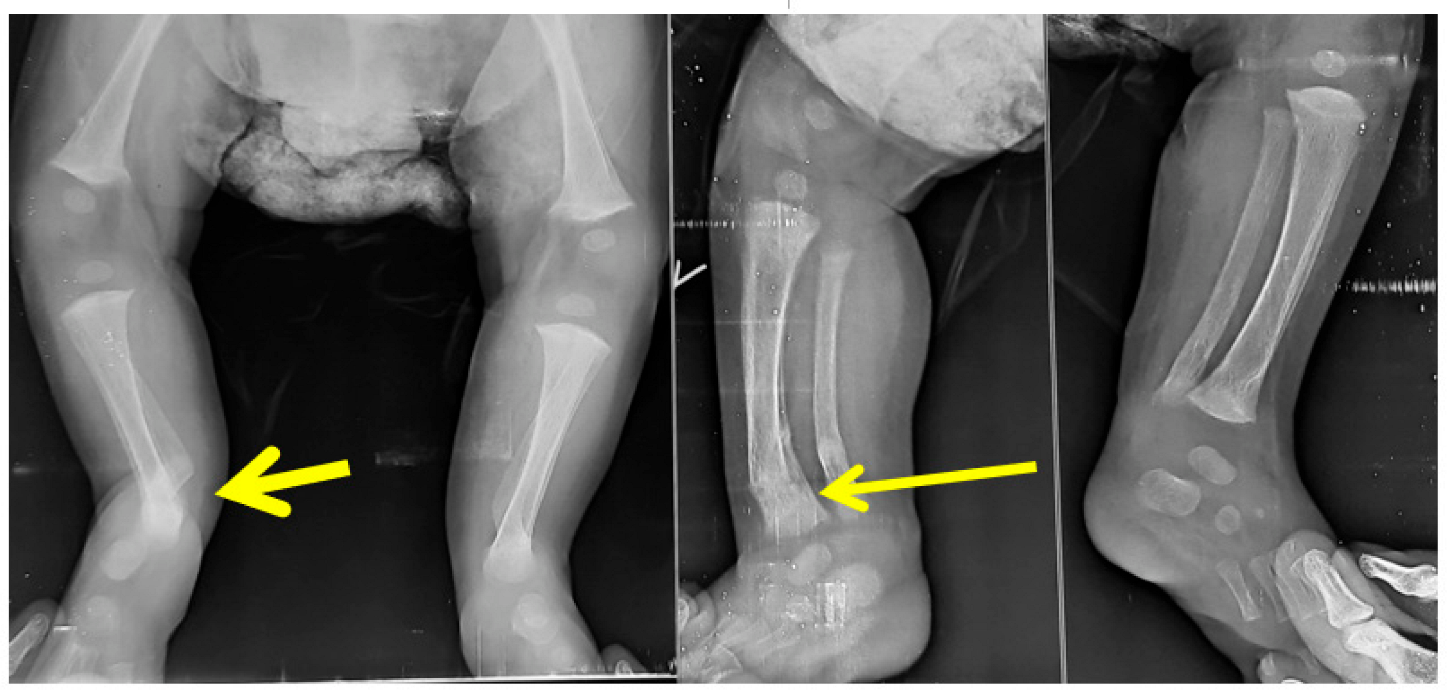

- Errors in diagnosis:

- Errors in manipulation: